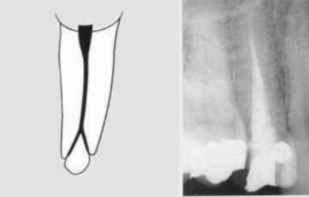

type 3

(2)

two separate canals leaving the pulp chamber and exiting from the root in separate apical foramina